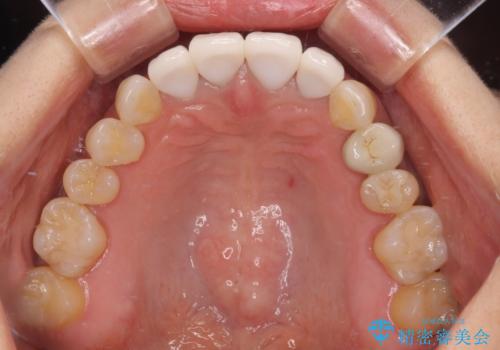

左右対称で明るく自然な前歯に仕上げることができました。